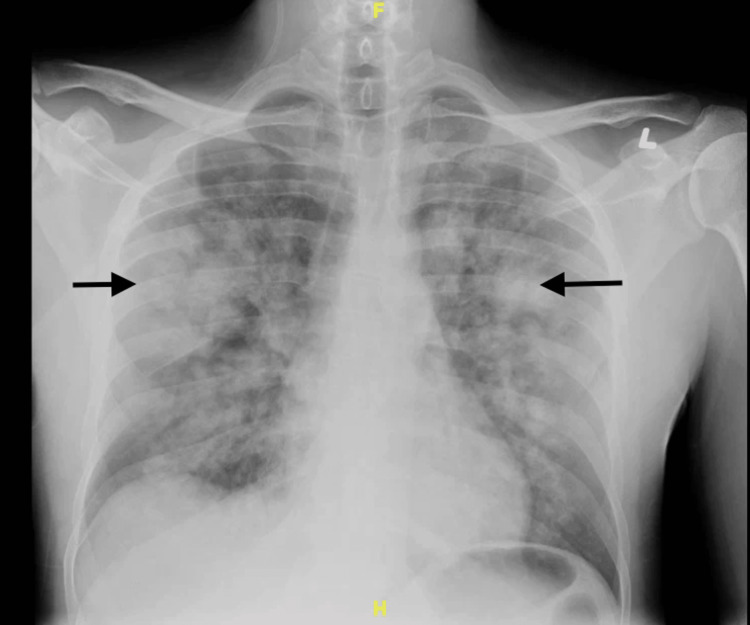

A 34-year-old male with a past medical history of asthma, hypertension, sickle cell trait, alcohol use disorder, and self-reported K2/Spice use presented to the ED with a complaint of hemoptysis for one day. He also complained of a yellow productive cough and chest pain for four days. His SpO2 was 87% to 89% in room air, and he was placed on 4 liters/min of supplemental oxygen via a nasal cannula. A chest x-ray showed multiple ill-defined pulmonary masses and areas of consolidation (Figure 1).